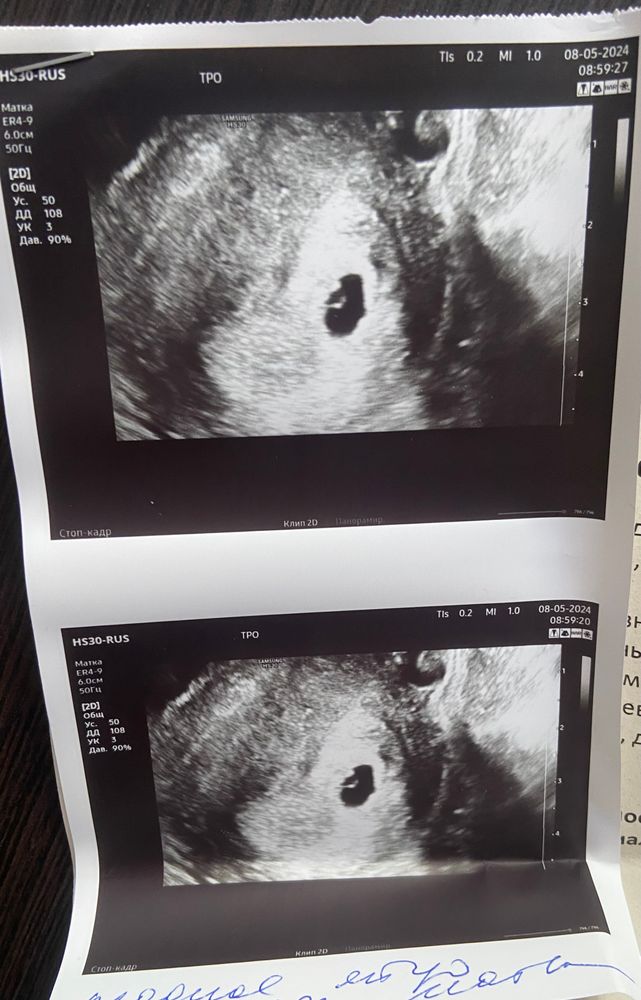

Первое УЗИ пройдено (для успокоения)🥰

УЗИ, КТГ, доплерДевочки, я так рада, что на этот раз ПЯ в матке, все соответствует и сроку и ХГЧ, придраться на данный момент не к чему, но вот гематома….в прошлую ЗБ тоже была, и кровотечение сильное. Тут Г сказала, что если что сразу дюфастон, если кровь пойдет , это сильно страшно?